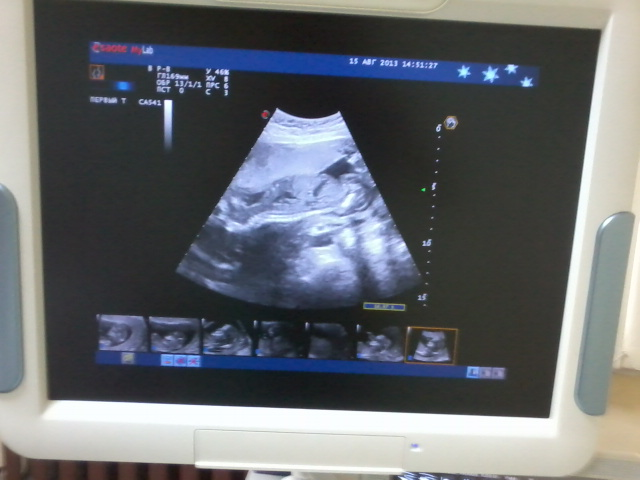

Сегодня ходила на УЗИ и оказалось,что в домике живёт у нас снова мальчуган.Видимо придётся в третий раз сходить в детский магазин за девочкой

Никак не пойму как малыш лежит.Лицом вниз?